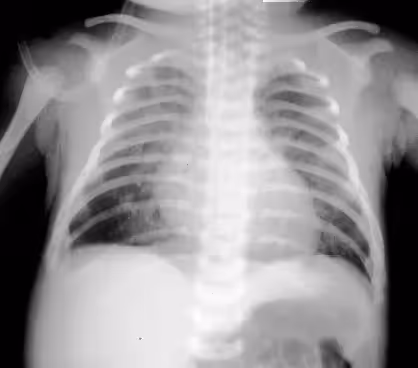

O raio X do indivíduo com síndrome do desconforto respiratório possui aspecto de vidro moído com broncograma aéreo (visualização clara dos bronquíolos preenchidos por ar, possível pela presença de infiltrado reticulogranular excessivo em volta) e a gasometria revela acidose mista.

Alterações gasométricas são raras e no Raio X encontra-se hiperinsuflação, congestão pulmonar, cisurite, vasos dilatados e, por vezes, derrame pleural. O diagnóstico da TTRN deve ser de exclusão, pois deve-se atentar para as causas mais graves antes, como pneumonia e doença da membrana hialina.

O raio X apresenta hiperinsuflação pulmonar, áreas de atelectasia alternando com áreas com opacidades assimétricas por todo tórax e a gasometria revela hipoxemia, com acidose respiratória ou mista.

O RN apresenta taquipneia, cianose e sinais de trabalho respiratório. em alguns casos pode haver distensão abdominal, icterícia e instabilidade térmica. O Raio X demonstra infiltração difusa retículo-granular com broncograma aéreo (os mesmos achados de uma SDR).